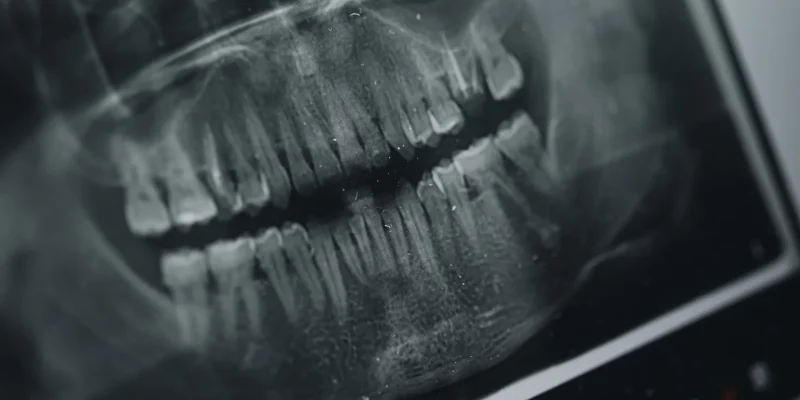

El diseño de sonrisa es un tratamiento odontológico estético que busca mejorar la forma, color y armonía de los dientes.

Puede incluir procedimientos como: